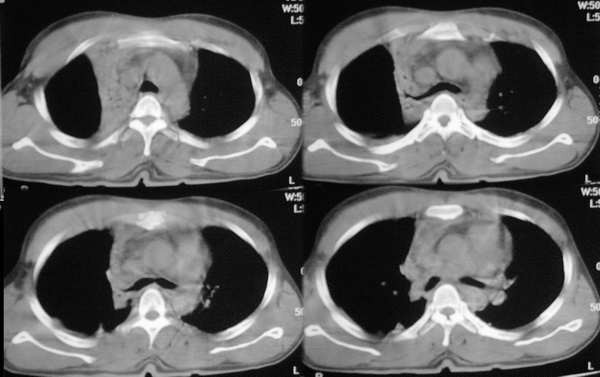

标题: CT2841:讨论.胸部外伤,是纵隔血肿还是心包积液? [打印本页]

标题: CT2841:讨论.胸部外伤,是纵隔血肿还是心包积液?

ssl1_1医生没有提供肺窗,从纵隔窗上看来似乎是右上纵隔增宽,但仔细观察发现病变边缘清楚锐利,右上叶支气管进入病灶内,病灶内可以见到残余气体密度影,所以必须要想到上叶肺不张的可能。在胸部外伤时,肺不张的发生原因是非常多而且复杂的,如支气管的断裂、管腔内血块或异物的阻塞、胸廓损伤导致呼吸肌无力、体位因素、脱水导致痰液不易咳出、胸腔积液的压迫等。心包和双侧胸腔均可见少量液体影,密度较高,应该考虑为少量积血。

该病例认为心包积液>纵隔血肿可能,其理由有以下几点:

3、主动脉弓以下大血管及心脏周围见环形低密度影,而主动脉弓以上大血管周边未见环形影。

4、从解剖学上看,纵隔包括心脏、大血管、气管、食管,是左右纵隔胸膜间全部器官、结构与结缔组织的总称,前界为胸骨,后界为脊柱胸段,两侧为纵隔胸膜,向上达胸廓上口,向下至膈肌。而心包为锥形纤维浆膜囊,包裹心和出入心的大血管根部,分为内、外两层,外层称纤维心包,内层称浆膜心包。纤维心包是坚韧的结缔组织囊,上方与在血的外膜相续,下方与膈中心腱愈着。浆膜心包分为两层:紧贴心和大血根部表面的浆膜为脏层,它在大血管根部移行为壁层,贴衬于纤维心包内面。脏、壁二层之间的腔隙称心包腔。

5、复习了解剖后,可以看出该病例的低密度影,始终围绕大血管及心脏,而大血管以血管未见明显低密度影。

看了12,13楼的分析受益非浅,肺窗右肺上叶不张.左下肺挫伤.